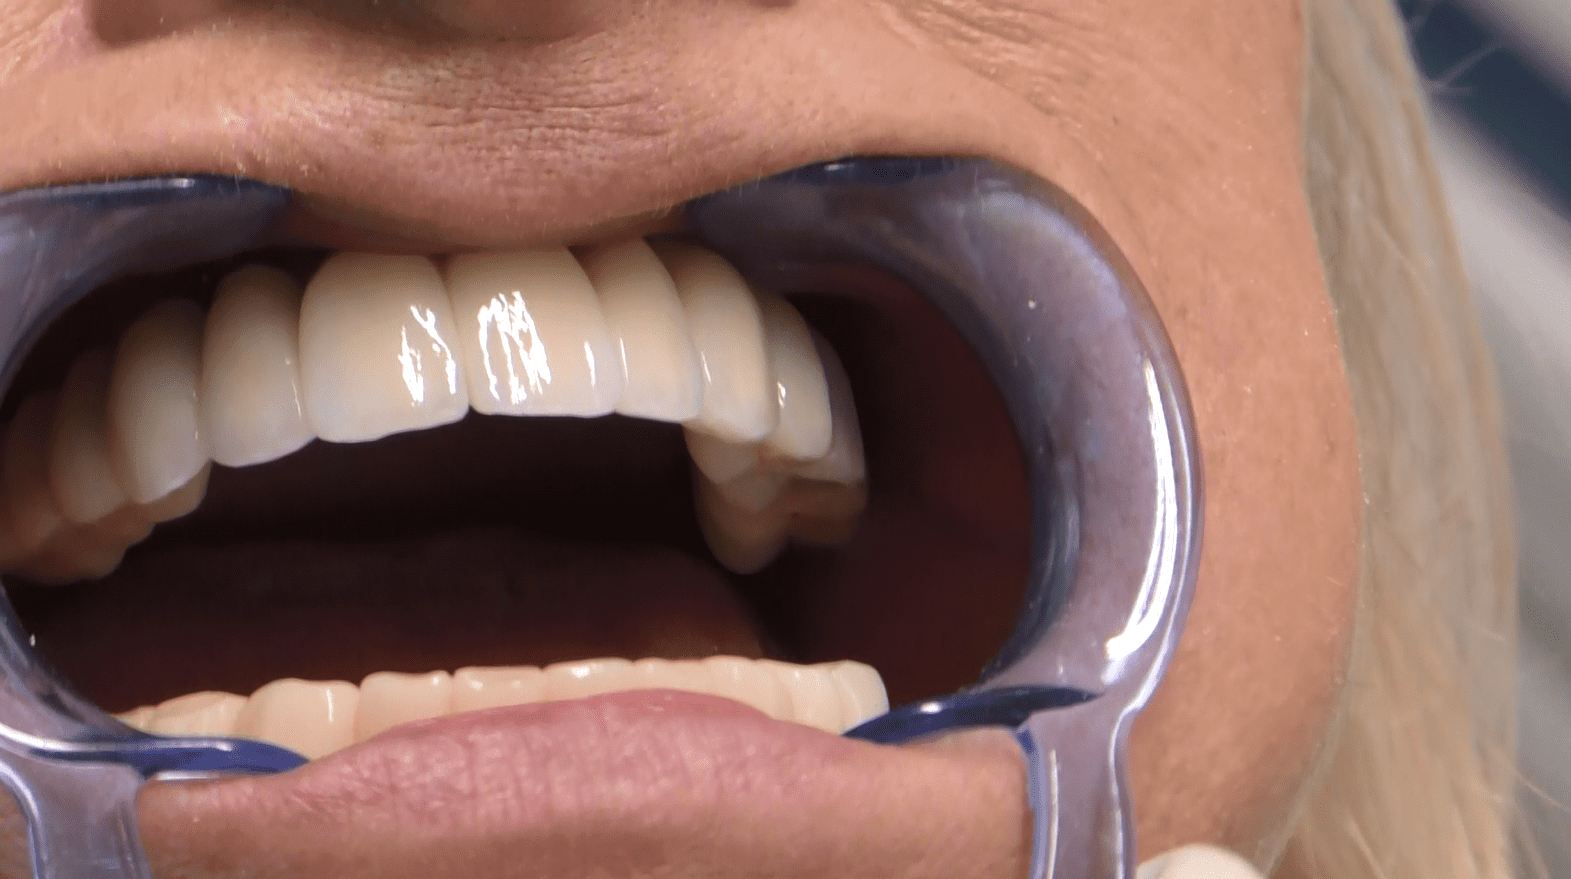

Protesi Circolare senza gengiva

“Protesi Circolare: Un Sorriso Naturale e Personalizzato Senza Confini”

Le nostre protesi circolari senza gengiva sono un capolavoro artigianale, realizzato su misura per ogni paziente. La forma circolare della protesi è studiata per adattarsi armoniosamente alla tua bocca, distribuendo uniformemente la pressione masticatoria e garantendo comfort e stabilità.

• La nostra firma è la protesi circolare senza falsa gengiva. Eliminiamo i confini artificiali per un sorriso che sembra naturale e autentico.

• La nostra galleria fotografica presenta una collezione di sorrisi trasformati grazie alle nostre protesi circolari. Scopri i risultati straordinari ottenuti per i nostri pazienti.